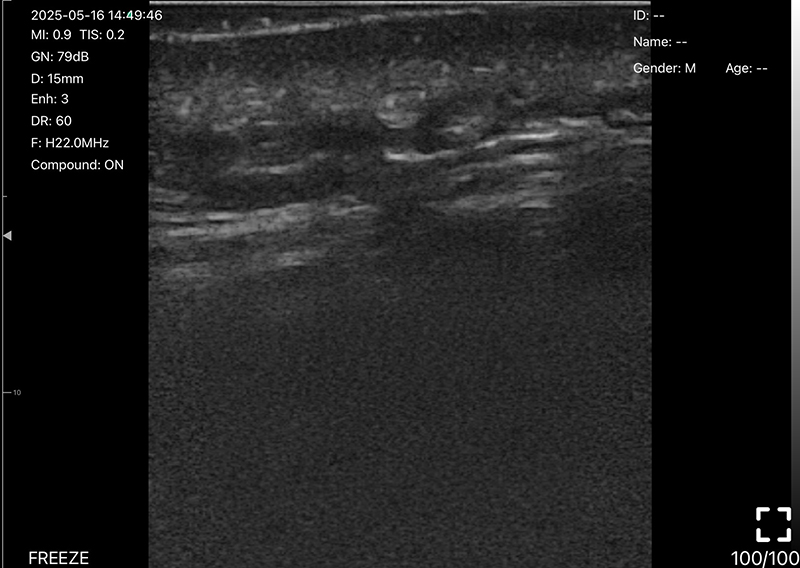

• 探头频率:10/13.2MHz

• 扫描深度:20/30/40/60mm,可调

• B模式

增益:30db-105db

降噪:0-1-2-3-4

动态范围: 40-50-60-70-80-90-100-110